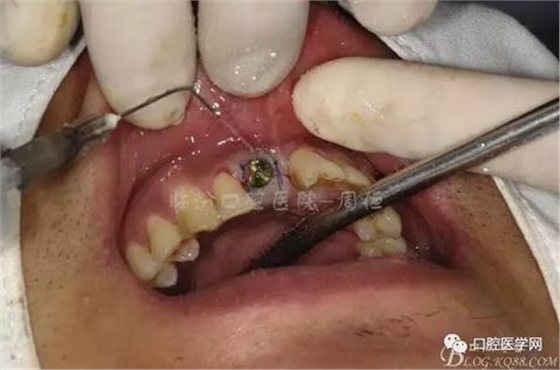

圖7 術(shù)后植入愈合基

圖8 術(shù)后即刻臨時(shí)冠修復(fù)